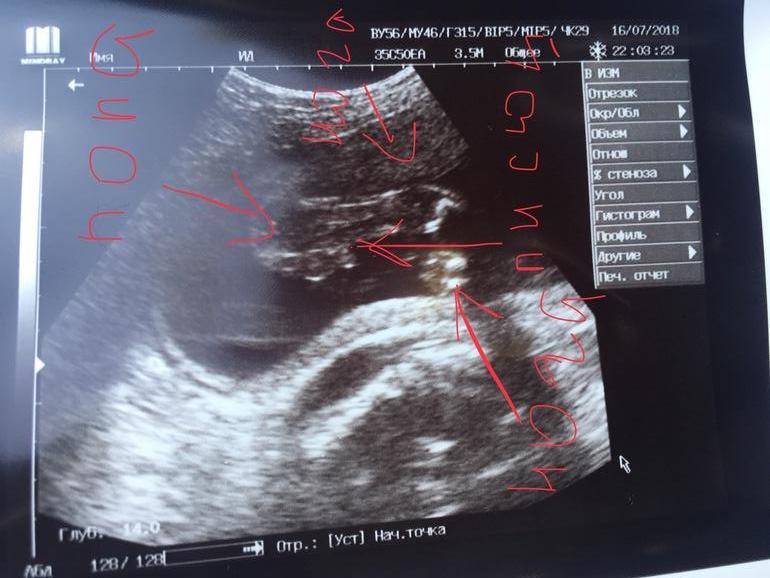

Тесты, ждем день ХЗдравствуйте на УЗИ сказали девочка но неуверенно. УЗИ 21 недели. А я вижу на фото писюн, как считаете кто?

Попа слева, нога более четкая сверху другая снизу, а вот то что между ними разве не похоже на писюн?

Подождите еще, и позже сходите на УЗИ! Возможно, у ребенка между ножек зажата пуповина)))